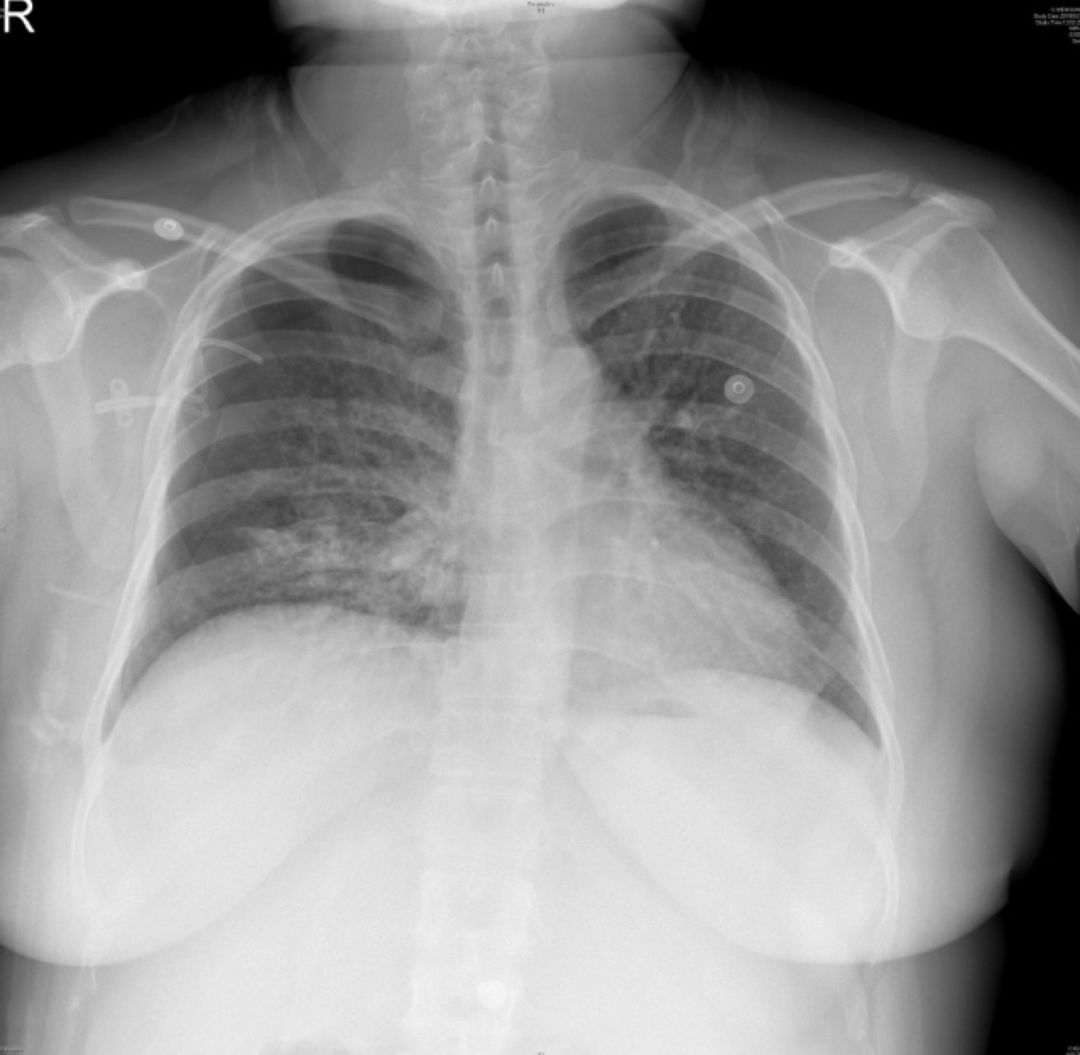

2019-5-21胸片:

2019-05-23床旁胸片:

1、治疗后患者体温平,复查CT提示气胸吸收,2019-05-26拔除胸腔闭式引流管,2019-06-06出院;